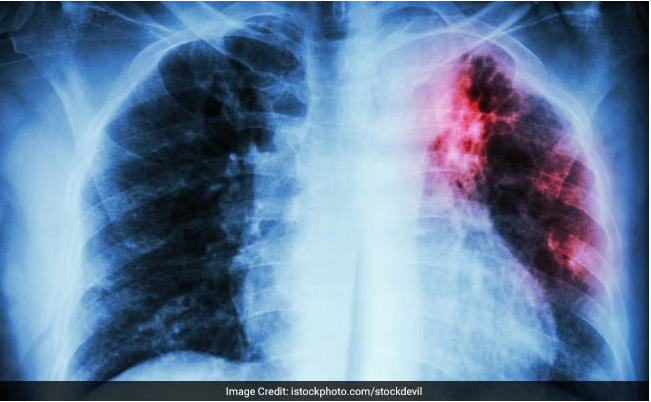

Tuberculosis is an infectious disease which can turn out to be fatal if not taken care of properly. It is caused by bacteria called Mycobacterium tuberculosis and people who are undernourished have a greater risk of developing TB. However, researchers have found a substance that may help combat this disease. The substance, called beta lactone EZ120, interferes with the formation of the bacterium's mycomembrane. The researchers found that the substance may inhibit the biosynthesis of the mycomembrane and kills mycobacteria effectively. The symptoms of Tuberculosis include weight loss, weakness and shortness of breath. However, consumption of certain foods can turn out to be beneficial for a tuberculosis patient.